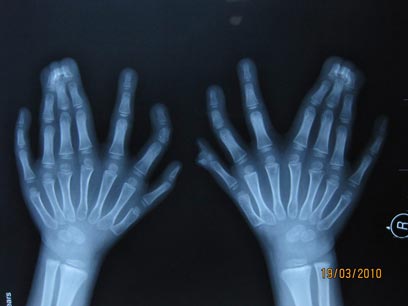

צילום רנטגן של אצבעות הידיים, חלקן דבוקות (צילום: AP)

התופעה נקראת פולידקטילי. אף שריבוי אצבעות כמו זה הוא נדיר יחסית, הרי שתופעת הופעת אצבע נוספת, לרוב זרת, אינה כה נדירה גם בארצנו, ומתרחשת אחת ל-700 לידות. אצל הילד נגרם עיוות שהביא ליצירת 15 אצבעות בשתי ידיו, ו-16 בהונות ברגליו. היום (ג') יעבור ניתוח להסרת האצבעות המיותרות.